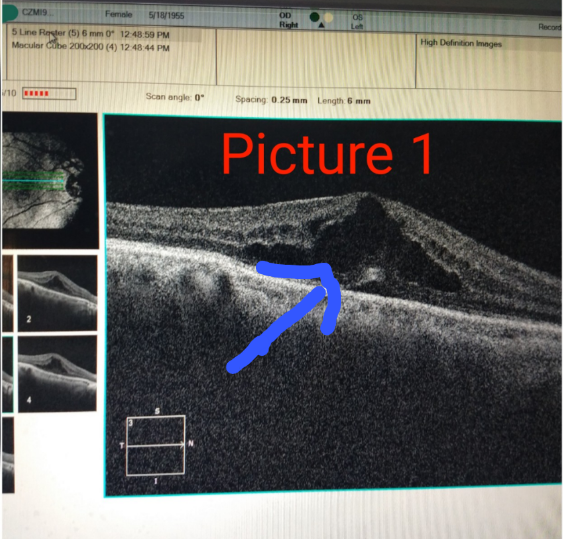

A 40 year old DIABETIC male came with complain of decrease in vision in left eye. On detailed eye examination, it was found that patient had macular edema ( collection of fluid in central part of retina). (Figures 1 and 2 - Red arrows). At that time patients vision in left eye was 6/24 (3 lines on vision chart). After 2 Anti - vegf injections inside the eye, patients vision improved to 6/6 (all the lines on vision chart). (Figure 3).